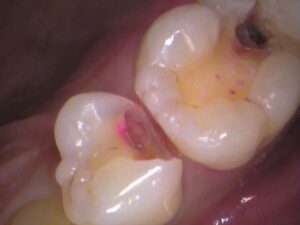

5番目の歯のレジンを取り除きました。

う蝕検知液という、虫歯を染色するお薬を塗って、虫歯をチェックします。

5番目の歯です。

赤く色が染まっている箇所が虫歯です(*_*)

やはりレジンの内部に虫歯が広がっていました。

赤い箇所の虫歯を削っていきます。